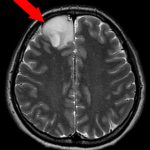

左脳腫瘍

頭蓋内腫瘍摘出術

No.’22_100 手術前1

No.’22_100 手術前2